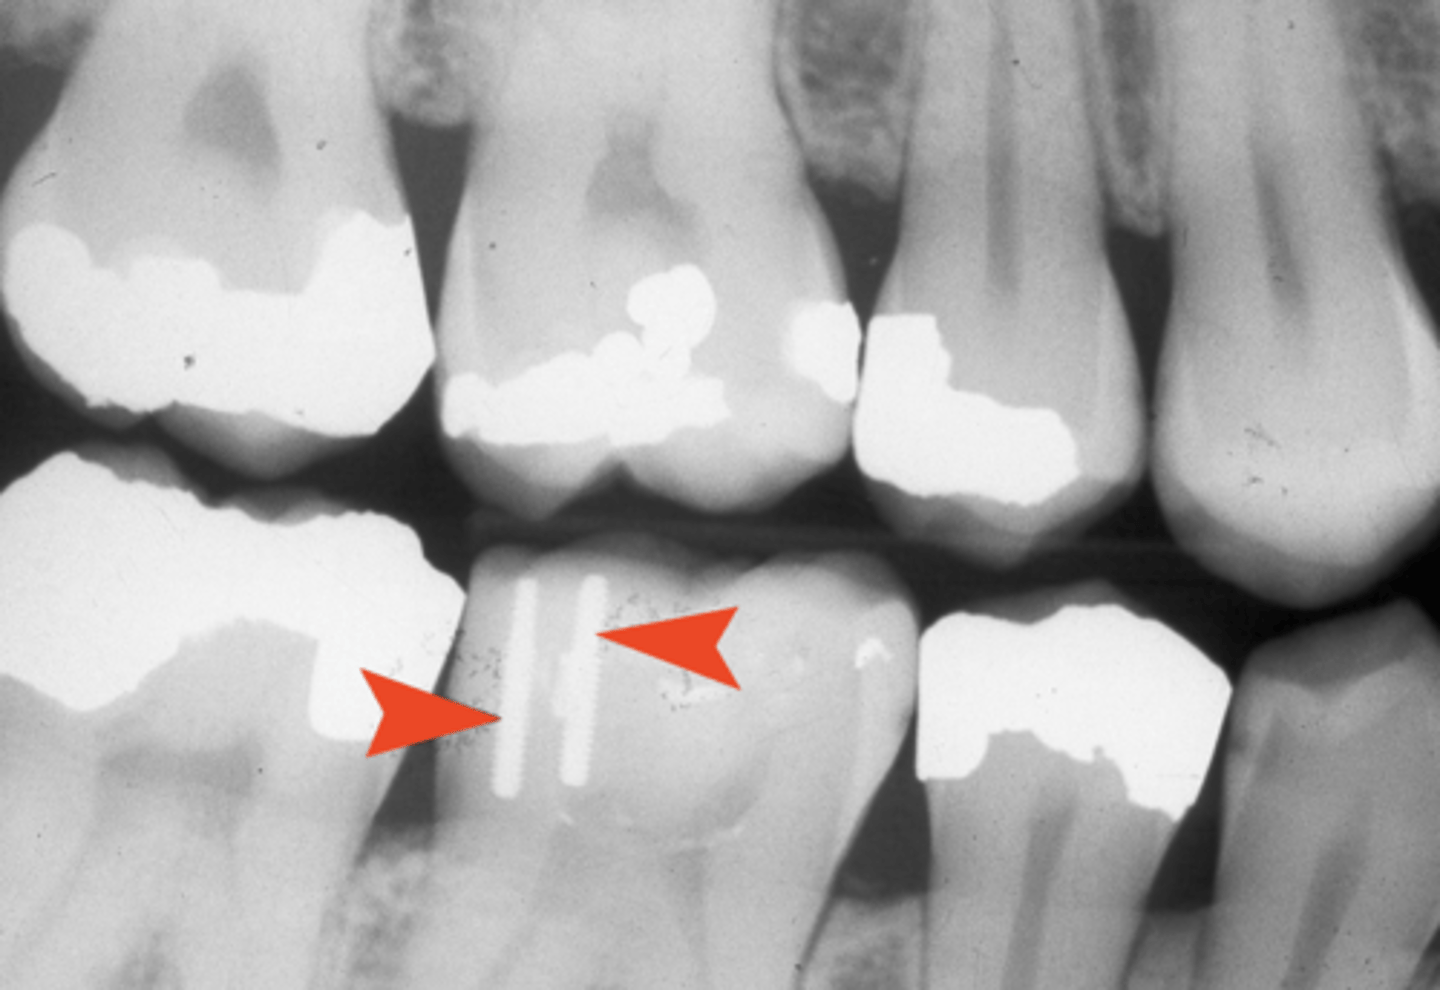

Post and core

- Metallic post and core that is cast at the lab

- Then seated in the root canal system and coronally to support tooth structure

Radiopaque materials

- Gutta percha: RC filling material

- > Very radiopaque

- Silver points: RC filling material rarely used anymore

Retention pins

Crown, amalgam, crown, cast post, gutta percha, and silver points location